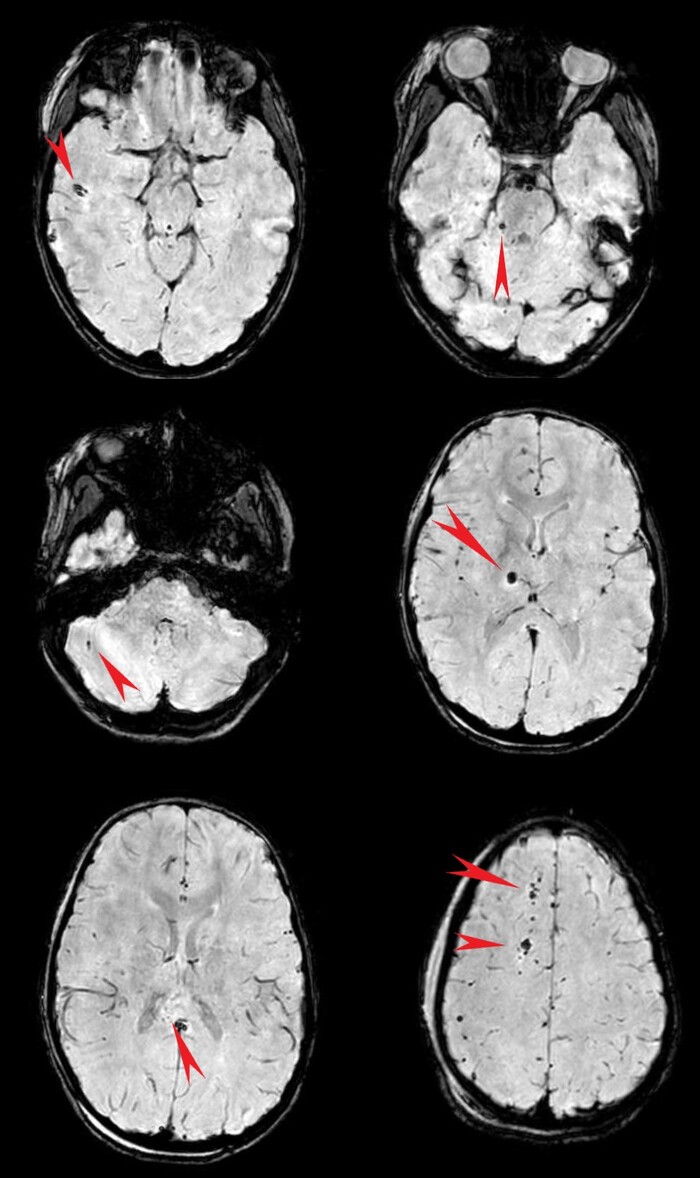

Ну и в довесок на SWI-изображениях (специальная импульсная последовательность, взвешенная по магнитной восприимчивости, усиливает сигнал от продуктов распада гемоглобина, что значительно повышает способность распознавать мельчайшие кровоизлияния в головном мозге) были выявлены очаги микрокровоизлияний в поражённых участках + в верхней ножке мозжечка и вдоль кортико-спинального тракта справа (чёрные пятна на изображениях):